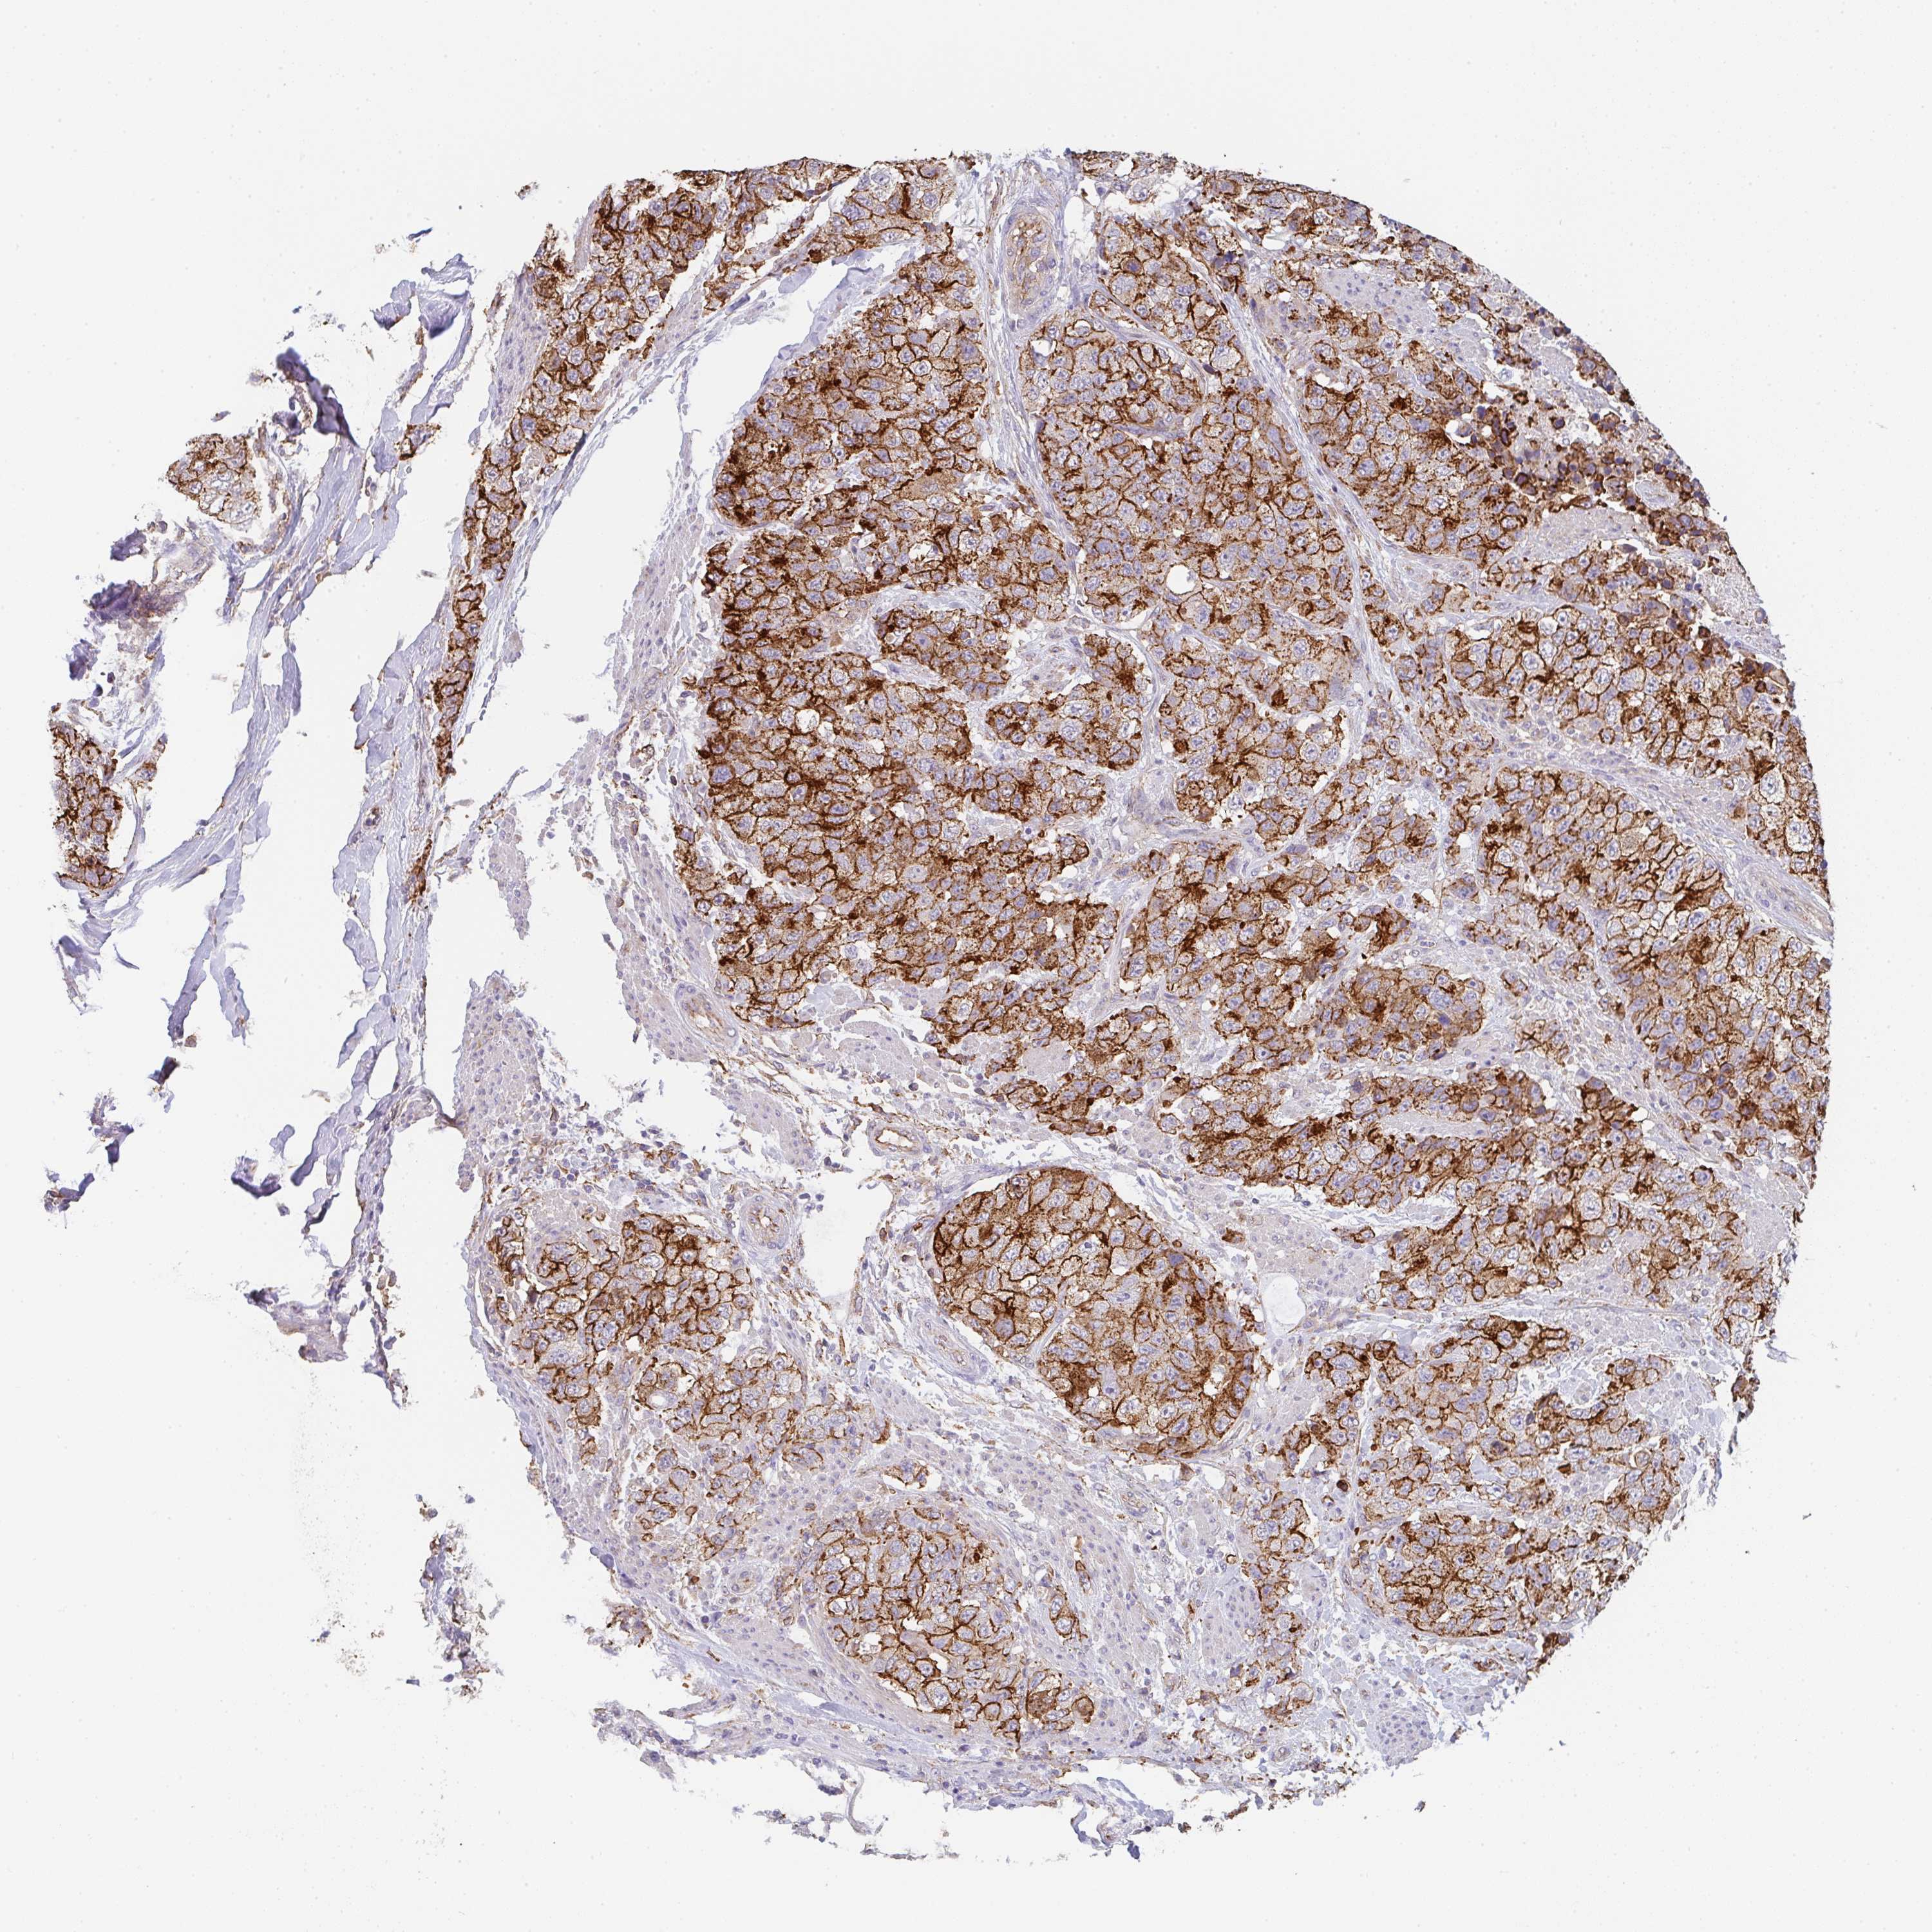

UROTHELIAL CANCER - Protein expressioni

A mouse-over function shows sample information and annotation data. Click on an image to view it in a full screen mode. Samples can be filtered based on level of antibody staining by selecting one or several of the following categories: high, medium, low and not detected. The assay and annotation is described here.

Antibody stainingi

Antibody staining in the annotated cell types in the current human tissue is reported as not detected, low, medium, or high, based on conventional immunohistochemistry profiling in selected tissues. This score is based on the combination of the staining intensity and fraction of stained cells.

Each image is clickable and will lead to virtual microscopy that enables deeper exploration of all samples and also displays staining intensity scores, fraction scores and subcellular localization as well as patient and tissue information for each sample.

Antibody HPA051452

Antibody HPA056940

Staining

High

Medium

Low

Not detected

Intensity

Strong

Moderate

Weak

Negative

Quantity

>75%

75%-25%

<25%

None

Location

Nuclear

Cytoplasmic/membranous

Cytoplasmic/membranous,nuclear

Urothelial carcinoma, High grade